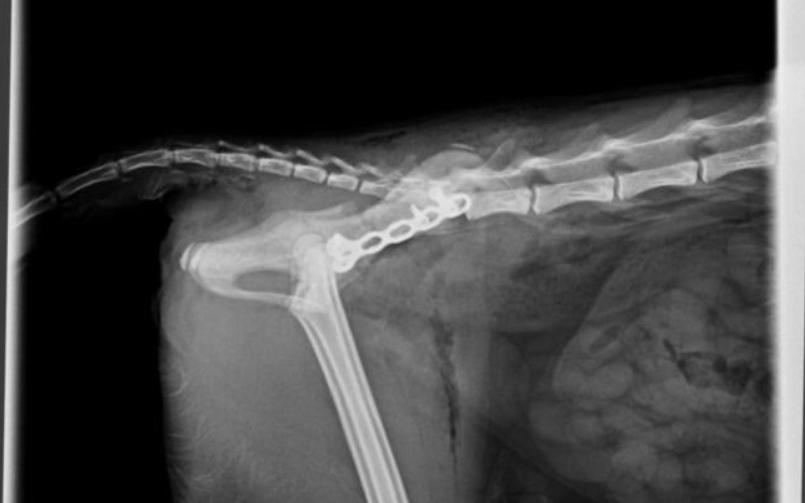

Kotka została znaleziona pod blokiem przez cudowną osobę, która nie pozostała obojętna i natychmiast powiadomiła odpowiednie służby! W wyniku upadku Felcia odniosła bardzo poważne obrażenia: przesunięcie kręgów w odcinku krzyżowym kręgosłupa, złamanie miednicy i zwichnięcie stawu biodrowego. Na szczęście zachowała czucie, więc mamy wielką nadzieję na powrót małej do pełnej sprawności, do czego długa droga...

Kicia jest już pod opieką naszej fundacji! Jest już po skomplikowanej operacji, której podjął się znakomity ortopeda, doktor Kacper Weigel. Z całego serca dziękujemy Panu doktorowi oraz całemu zespołowi Kliniki Weterynaryjnej Puławska za błyskawiczną pomoc i zaangażowanie! Wszystko się udało i po 6 tygodniowym unieruchomieniu w kennelu rozpoczniemy rehabilitację.